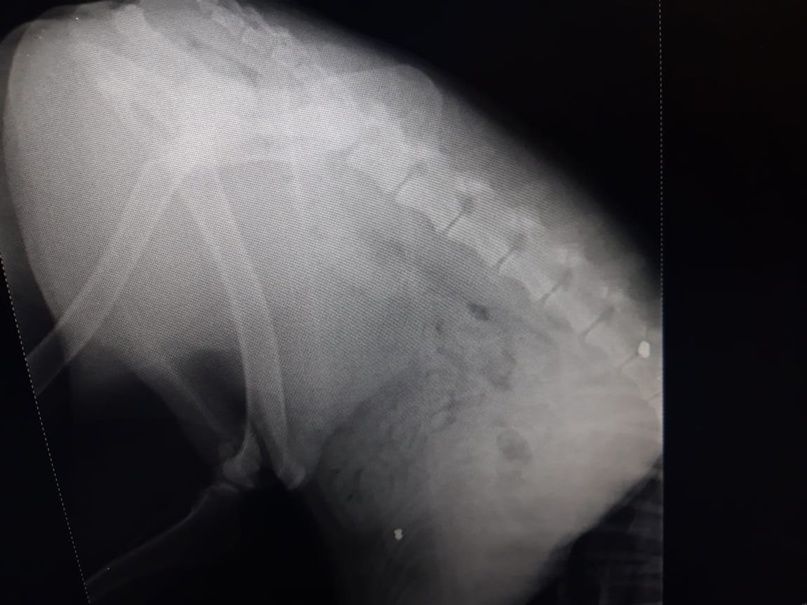

Окровавленную собаку нашли в районе домов № 23, № 25 на улице Алексеева. Пёс не мог самостоятельно передвигаться, и поначалу волонтёры подумали, что его сбила машина. Однако рентген показал, что в позвоночнике и в бедре животного застряли две пули.

Бобик жил у лицея № 4 и часто играл с детьми. Сейчас он в ветеринарной клинике Воронежа. Врачи извлекли пулю из позвоночника пса, которая сильно повредила спинной мозг. Есть шанс, что животное будет ходить, так как у него сохраняется чувствительность в лапах. Вторая пуля пока не извлечена.